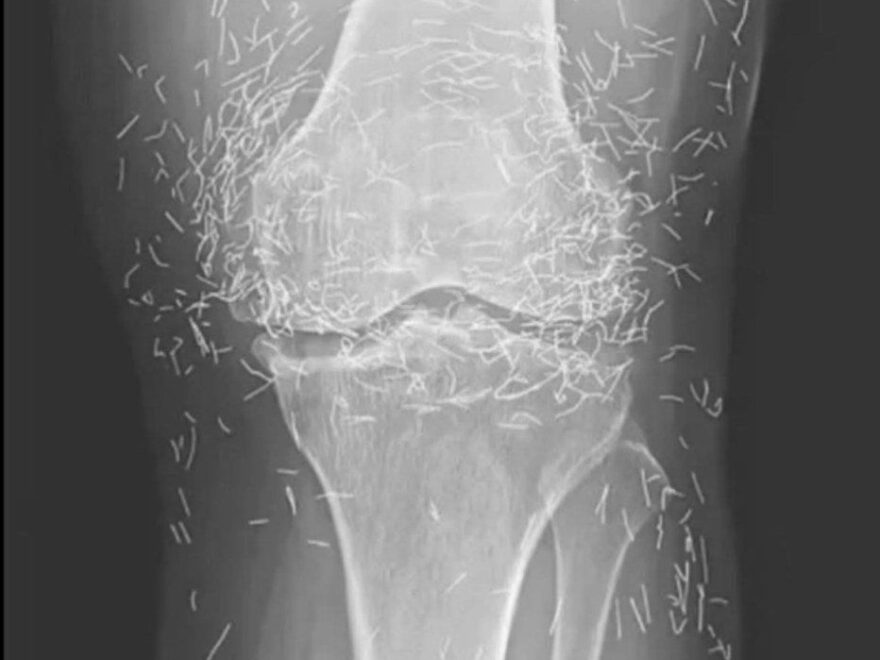

Years later, when doctors took X-rays to evaluate her knee condition, they weren’t prepared for what appeared on the images. Her knees were filled with dozens of bright, metallic flecks — tiny needles embedded deep within the joint area.

The findings were later documented in a case published by the New England Journal of Medicine.

Even more concerning, the presence of metal inside the body can make certain scans dangerous. MRI machines rely on powerful magnetic fields, and embedded needles may shift during scanning, potentially damaging blood vessels or surrounding tissue. In short, future diagnostic options for this patient became limited.